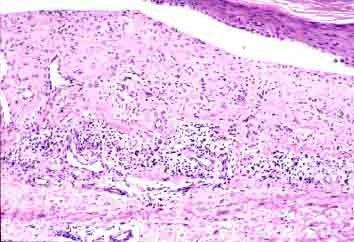

1、皮肤症状:以下肢大关节附近及臀部分批出现对称分布、大小不等的斑丘疹样紫癜为主,主要分布于下肢的伸侧和臀部,常为对称性,少数累及面和躯干部。紫癜可突出皮面、伴轻微痒感,初为鲜红色,继而为暗红色、褐色,亦可以表现荨麻疹、血管神经性水肿、多形红斑,甚至溃疡坏死和出血性大疱等。皮疹大小不一,可融合成片,分批出现,亦可反复发作,有的可伴有局限性或弥漫性水肿,如头部、面部、眼睑等。皮肤紫癜通常约经过2周而渐消退。

皮肤紫癜:皮肤和粘膜出血后颜色改变的总称。临床表现为出血点、紫癜和瘀斑,一般不高出皮面,仅于过敏性紫癜时可稍隆起,开始为紫红色,压不退色,以后逐渐变浅,至两周左右变黄而消退。